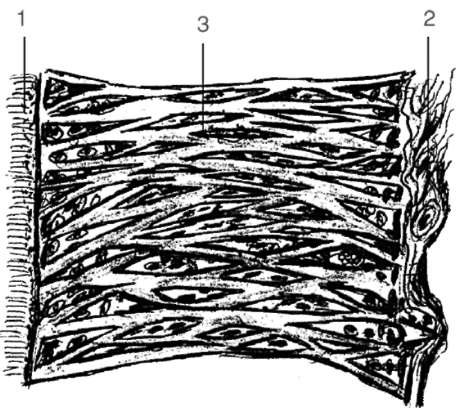

Рис. 4-3. Коллагеновые волокна, проникающие в вещество цемента (Гемонов В.В.)

Рис. 4-4. Схема строения коллагеновых волокон периодонта зубов человека (Гемонов В.В.): 1 - цемент корня зуба; 2 - кость альвеолы; 3 - пучки коллагеновых волокон в виде сетки гамака